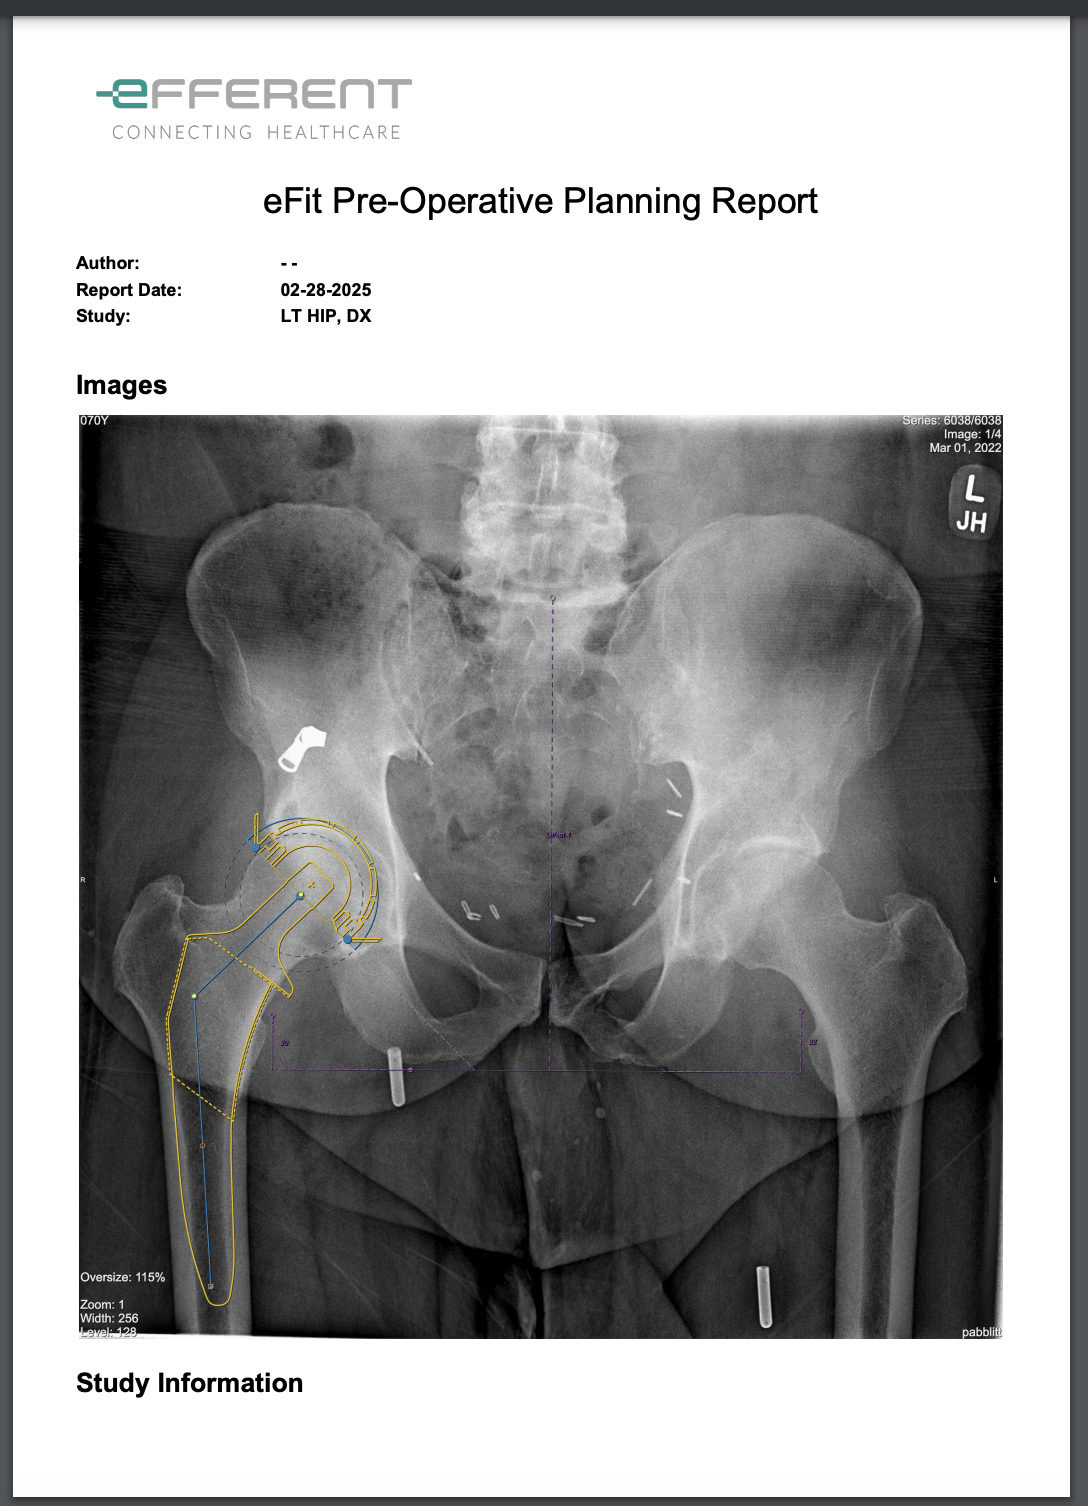

New DICOM image generation in eFit

eFit now creates a new DICOM image in a separate series when saving a template. This image contains the implant planning information for hip and knee templates, ensuring compatibility with external DICOM viewers.

Template Image Integration in eFit Reports

eFit reports now display images of the generated hip and knee templates. Previously, reports did not support image visualization. With this update, template images are automatically included, improving documentation and clarity.